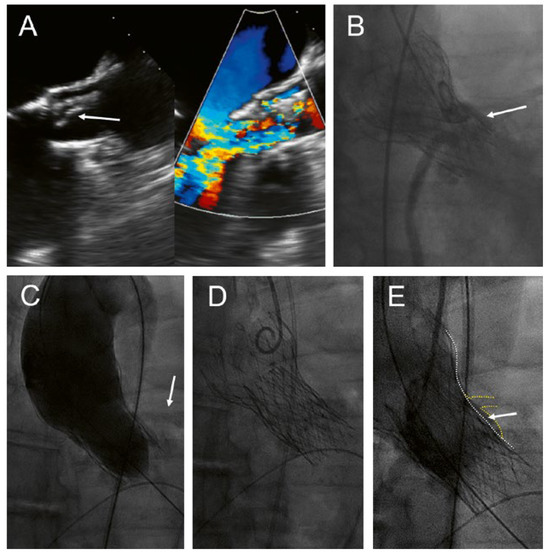

A 68-year-old man presented with increasing shortness of breath and a history of decompensated heart failure 8 years aher transfemoral implantation of a CoreValve 29 mm for severe, calcified aortic stenosis. Transthoracic and transoesophageal echocardiography revealed a partial tear-off and prolapse of one of the bioprosthetic leaflets of the CoreValve, with severe transvalvular and mild paravalvular regurgitation and a mild stenosis with a mean gradient of 26 mm Hg (Figure 1A). The patient’s main comorbidity was a congenital Laurence-Moon-Bardet-Biedl syndrome with blindness and obesity (body mass index 49 kg/m2). The patient was on rivaroxaban for persistent atrial fibrillation. Coronary angiography showed patent coronary arteries but a very shallow aortic sinus with a substantial risk of coronary obstruction (Figure 1B). In the presence of negative blood cultures and an unremarkable positron emission tomography (PET) scan, active endocarditis was very unlikely.

The patient was discussed in the interdisciplinary HeartTeam. The decision was to repeat the transcatheter aortic valve implantation with an Allegra transcatheter heart valve (THV) (NVT AG, Muri, Switzerland and NVT GmbH, Hechingen, Germany). Before implantation of the Allegra, a 22-mm TrueDilatation balloon was inflated and a supra-annular injection was performed to ensure patency of the coronary arteries (Figure 1C). Thereaher, an Allegra 27 mm was implanted about 6 mm below the inflow portion of the CoreValve (Figure 1D). Postdilatation was performed with the 22-mm TrueDilatation balloon. Postprocedural course was uneventful. Echocardiography before discharge showed a mild paravalvular leak and a mean gradient of 18 mm Hg; the calculated aortic valve area was 1.7 cm2.

Figure 1. Implantation of an Allegra valve in a degenerated CoreValve. This patient presented with severe transvalvular aortic regurgitation due to partial tear-off and prolapse of one of the leaflets (A, arrow). The aortic sinus was narrow with a high risk of coronary obstruction (B, arrow). An injection was performed during inflation of a 22 mm balloon to assess patency of the coronary arteries (C, arrow). Final position of the Allegra 6 mm below the inflow portion of the CoreValve (D), with only minimal space (E, arrow) between the frames of the transcatheter valves (E, white dotted line) and the sinus/left main coronary artery (E, yellow dotted line).